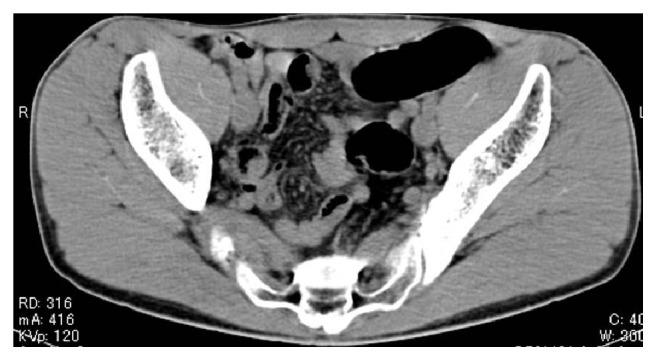

Radiologic diagnosis of colorectal foreign bodies is usually not very difficult, because inserted materials are often clearly visible on plain abdominal radiographs. However, when they are radiolucent, a plain abdominal radiograph has been reported to be useless. As radiolucent colorectal foreign bodies appear as radiolucent artificial contours or air-trapped materials in the pelvis, almost always the diagnosis itself can be made by careful evaluation of plain abdominal radiographs. We encountered a case of casting type of radiolucent colorectal foreign body formed from polyurethane foam. It presented us with unexpected radiologic findings and led to diagnostic difficulties.

结直肠异物的放射学诊断通常不是很困难,因为插入的异物在腹部平片上往往清晰可见。然而,当异物为透射线时,据报道腹部平片并无诊断价值。由于透射线的结直肠异物在骨盆中表现为透射线的人工轮廓或气体包裹物,几乎总是可以通过仔细评估腹部平片来做出诊断。我们遇到一例由聚氨酯泡沫形成的铸型透射线结直肠异物病例。它给我们带来了意想不到的放射学表现,并导致了诊断困难。